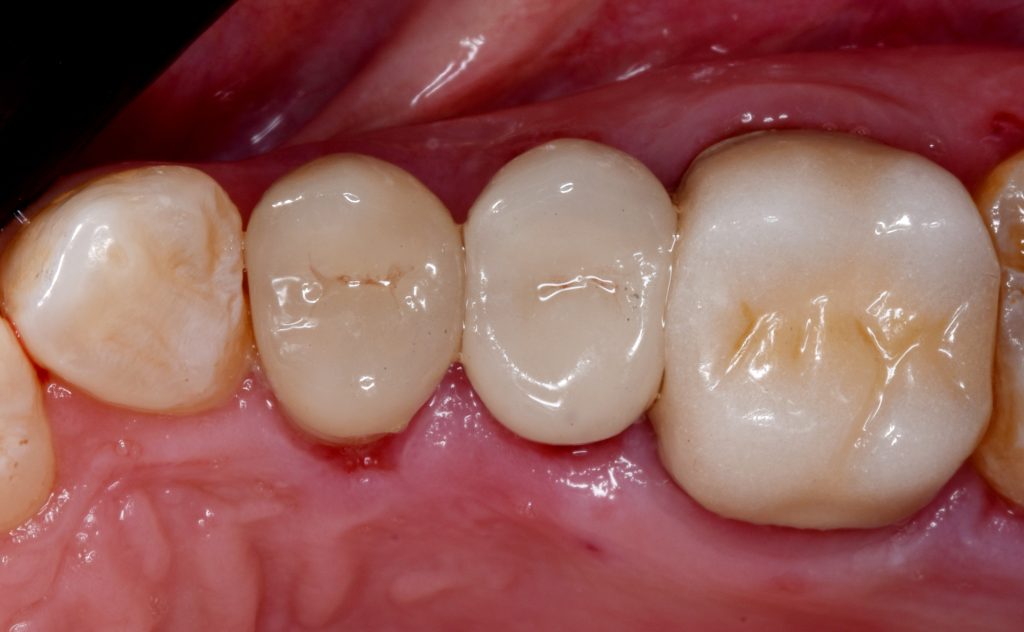

Upper right first and second premolars

And final design to receive to monolithic lithium disilicate restorations

Cementation by heated composite

Shofu beautifill LS